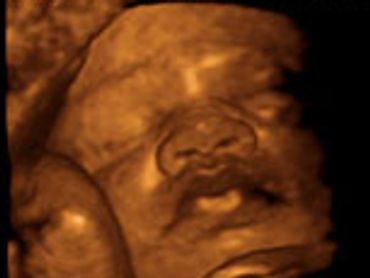

All our providers do their own ultrasounds in the office during your visit. We are known for our ultrasounds and do at least four with each pregnancy. And we can record your ultrasound on a USB device for you to take home and share!